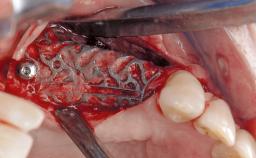

Paolo Casentini demonstrates that peri-implantitis can be successfully treated even at an advanced stage. He discusses a case in which the existing implants and prostheses were both retained while regenerating the defect and creating a band of keratinized tissue. A 69-year-old female patient was referred by her general dentist for evaluation of a recurrent infection at previously placed and restored implants in the posterior left mandible. The patient’s chief complaint was recurrent swelling and pain in the molar region of the left posterior mandible with discomfort during brushing in the same area. The patient reported receiving two implants (36 and 37) nine years earlier.